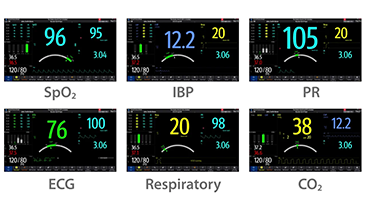

Sinds de oprichting van het bedrijf is Mindray voortdurend op zoek naar nieuwe manieren om het diagnostisch vertrouwen te vergroten. Resona 7 wordt aangestuurd door de meest revolutionaire ZONE Sonography?-technologie. Zijn nieuwe ZST+-tilt de kwaliteit van ultrasoundbeeldvorming naar een hoger niveau door middel van zoneacquisitie en kanaalgegevensverwerking.

Naast de hoogwaardige beeldvormingskwaliteit verbetert de Resona 7 tevens de klinische onderzoeksmogelijkheden met de revolutionaire V Flow voor vasculaire hemodynamische evaluatie, en de intelligentste vlakacquisitie van een 3D-gegevenssets voor de diagnose van het foetale, centrale zenuwstelsel. Met zijn combinatie van de meest intu?tieve, op vingerbewegingen gebaseerde multi-aanrakingsbediening en alle essenti?le klinische functies loopt de Resona 7 voorop in de nieuwe golven van ultrasoundinnovatie.